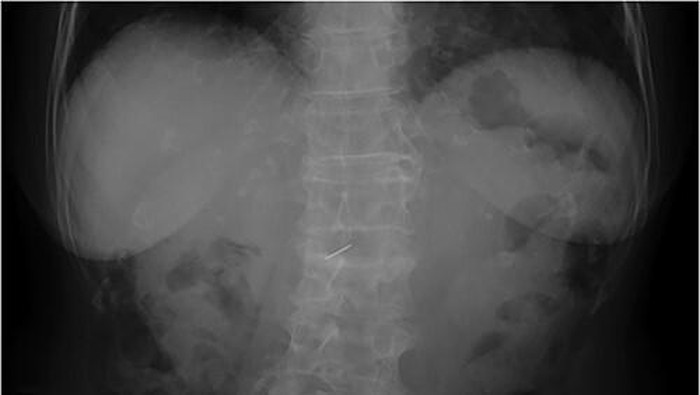

Jakarta - Dokter di Jepang menemukan jarum jahit 3 cm di hati nenek 81 tahun saat cek pencernaan. Ternyata jarum tersebut bisa masuk ke dalam tubuh lewat ini.

Penampakan Jarum Jahit Nyangkut di Liver Nenek Umur 81, Masuk Lewat Mana?

Jarum jahit sepanjang sekitar 3 cm berhasil diangkat melalui operasi laparoskopi. Pasien pulih dengan baik dan dipulangkan empat hari setelah operasi tanpa komplikasi. (Foto: Journal of Surgical Case Reports)